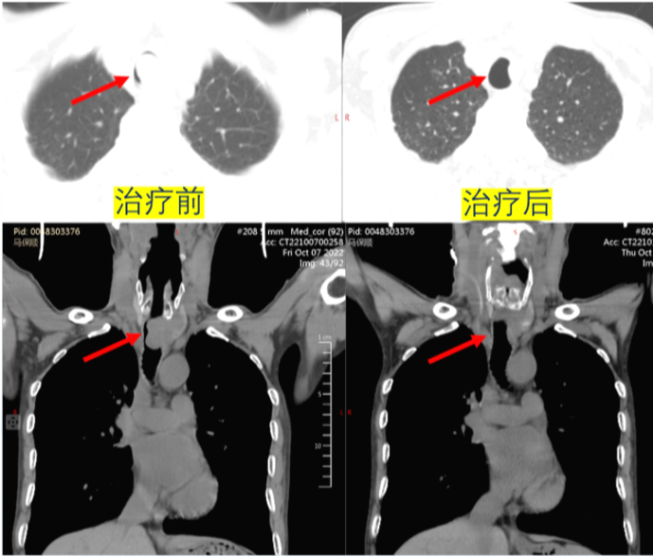

病例2:危重的恶性气道狭窄

一般情况:男性,56岁,气管腺样囊性癌2年,未正规治疗。气短3天,逐渐加重。

查体:胸闷气短,端坐呼吸,指脉氧下降,三凹征明显,气管听诊区可闻及双相哮鸣音,PaO2 50 mmHg。镜下可见气管内新生物堵塞气道(图11)

MDT意见:①无法外科手术;②端坐呼吸、气短明显,全麻风险极高;③肿块组织大,硬镜旋切出血及管腔阻塞的风险极大。在此情况下,治疗团队选择了一种既能降低手术风险,又可以处理大气道阻塞的方法——清醒VV-ECMO+硬镜旋切。切除的肿瘤组织较多且大,呈黏液样表现(图12)。手术前后对比发现,患者气道狭窄明显改善(图13)

图13  患者手术前后比较